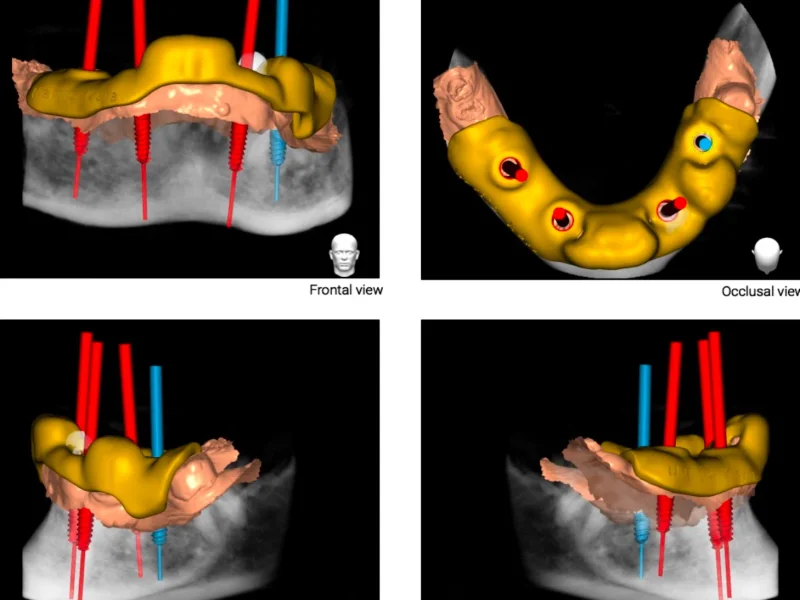

- –CBCT snimanje zubi(Najprecizniji oblik dentalnog snimanja koji omogućuje trodimenzionalni prikaz zuba, kosti i okolnih struktura. Koristi se najnovija digitalna CBCT tehnologija s niskom dozom zračenja i iznimnom rezolucijom. Precizan prikaz do 0,01 mm, veliko polje snimanja (do max. 20x17 cm).)